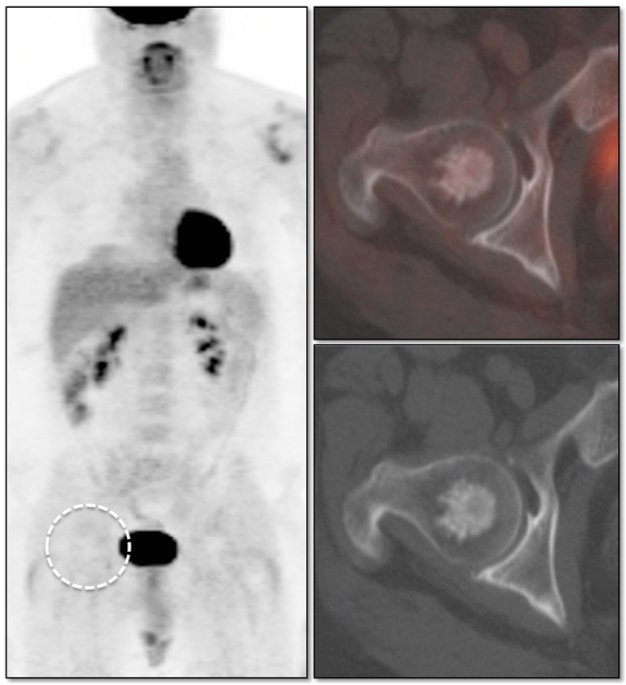

Vertebral Body Hemangioma:

Vertebral body hemangiomas are regularly seen on PET/CT scans and are non-avid.

On CT images, they classically demonstrate a “striated” appearance on sagittal images and a “stippled” appearance on axial images.

While the CT appearance alone is usually diagnostic for hemangiomas, there are cases when it is reassuring to confirm the diagnosis by an absence of metabolic activity on the PET portion of the exam (particularly for those cases where a prior MRI has been equivocal, suggesting the possibility of an “atypical hemangioma”).